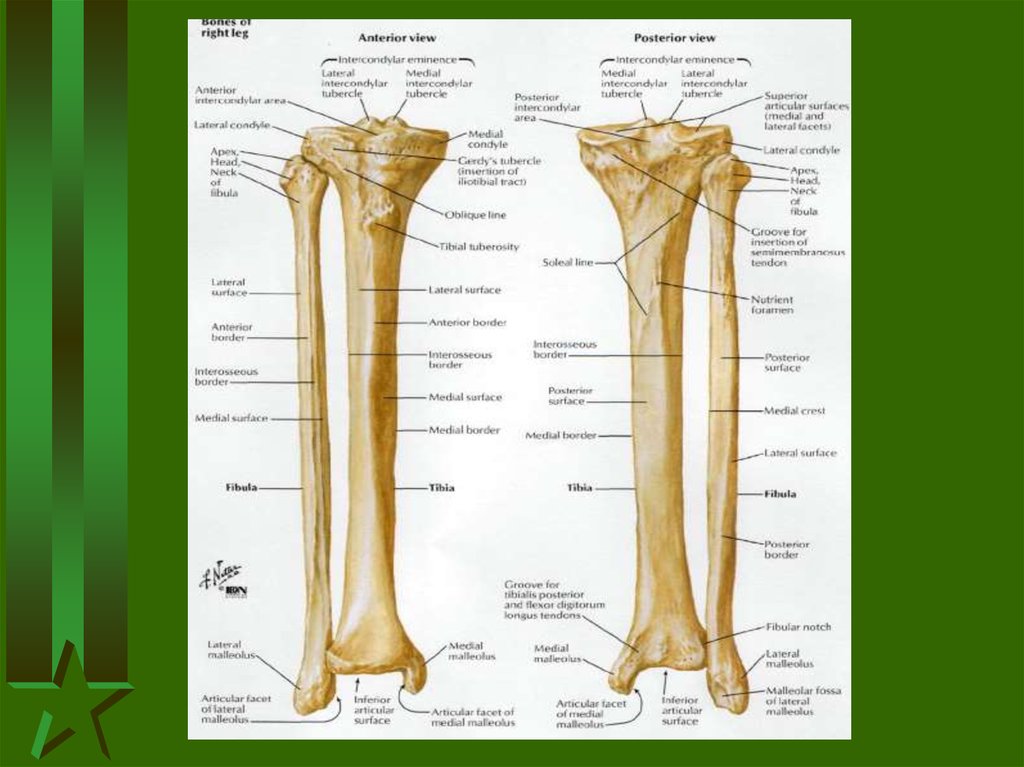

Загальна остеологія